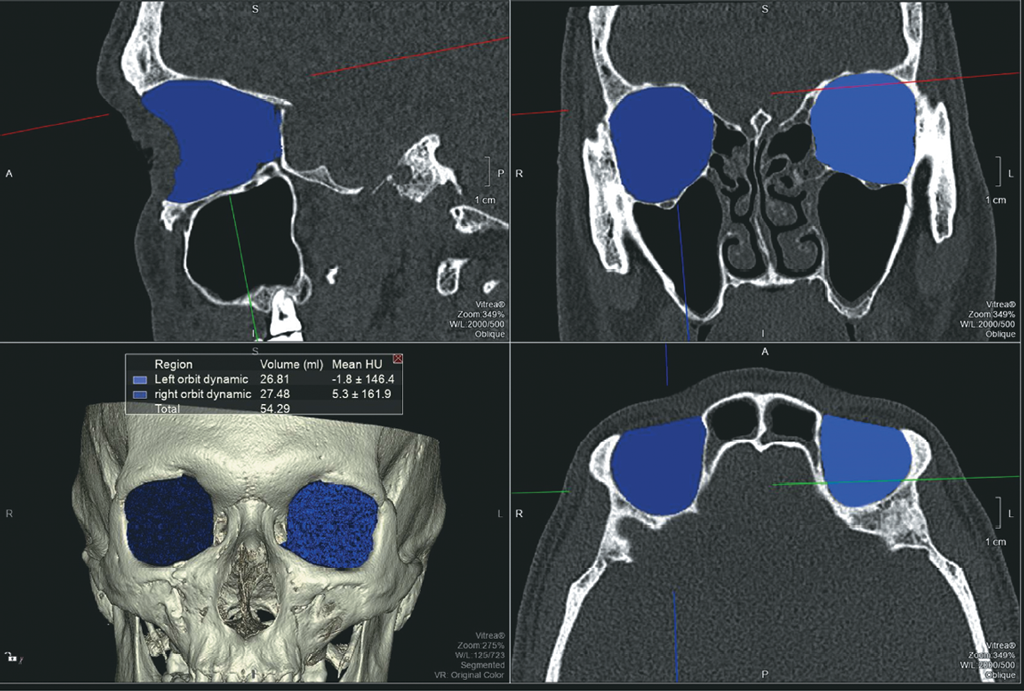

- На каждом аксиальном срезе выполняли маркировку всех костных границ орбит, начиная с верхней стенки до уровня дна орбиты (рис. 2). Для точности измерения необходимо чётко соблюдать костные границы и учитывать анатомические вариации строения, а также участки повреждения целостности стенок орбиты.

Рис. 2. МСКТ, средняя зона лица, костный режим. Аксиальная (a) и 3D-реконструкция (b). Маркировка костных границ орбиты

Fig. 2. MSCT, midface, bone window. Аxial (a) and 3D (b) reconstruction. Marking of orbital bone borders

При подсчете объёмов поврежденной и здоровой орбит у данного пациента разница объёмов после травмы составила 0,4 мл (рис. 5). По литературным данным считается, что при разнице объёмов орбит более 2 мл западение глазного яблока увеличивается на 1 мм и, как следствие, повышается риск развития энофтальма. Таким образом, у данного пациента риск развития посттравматического энофтальма минимален. Ввиду отсутствия нарушений зрительных функций и осложнений со стороны костных и мягкотканных структур орбиты, у данного пациента проводили консервативную терапию и осуществляли динамический контроль в посттравматическом периоде.

Рис. 5. МСКТ, средняя зона лица, костный режим. Измерение объёмов орбит после травмы на рабочей станции. При подсчёте объёмов повреждённой и здоровой орбит у данного пациента разница объёмов в течение 48 часов после травмы составила 0,4 мл

Fig. 5. MSCT, midface, bone window. Orbital volume assessment after trauma at a workstation. Upon volume calculation of the affected and the normal orbit 48 hours after trauma in this patient, the volume difference was 0.4 ml

Для оценки изменения объёма правой орбиты нами была применена методика расчёта объёмов орбиты с помощью обработки МСКТ-изображений на рабочей станции (рис. 7). В позднем посттравматическом периоде разница объёмов травмированной и здоровой сторон составила 0,67 мл, что находится в диапазоне допустимых значений и свидетельствует о минимальном риске развития энофтальма.

Рис. 7. МСКТ, средняя зона лица, костный режим. Измерение объёмов орбит после травмы на рабочей станции. Измерение объёмов орбит через 2 года после травмы. В позднем посттравматическом периоде разница объёмов травмированной и здоровой сторон составила 0,67 мл

Fig. 7. MSCT, midface, bone window. Orbital volume assessment after trauma at a workstation 2 years after trauma. In the late post-traumatic period, the volume difference between the affected and the normal side was 0.67 ml